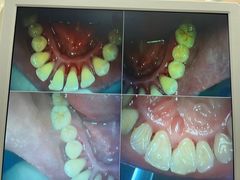

• 牙博士口腔品牌连锁(杨浦店)

• -牙博士口腔品牌连锁(杨浦店)

今创源 | 22-06-26